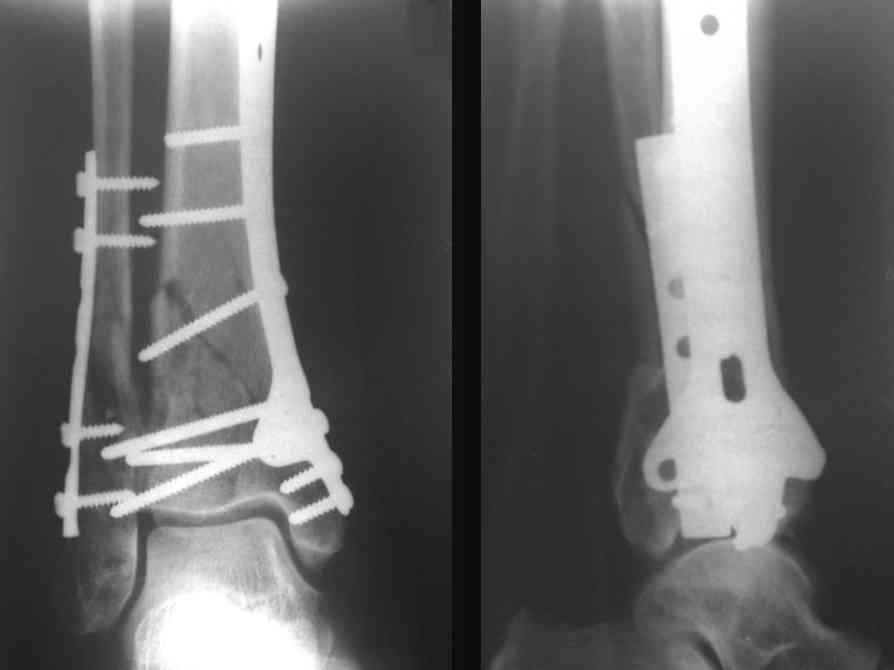

На рентгенограммах типичный перелом пилона по типу С-3. есть опыт до 100 открытых опреаций у нас в клинике. 20 примерно в год. Принцип один -все внутрисуставные переломы нуждаются в открытой репозиции и внутренней стабильной фиксации. При поступлении КТ не надо, так как получается только нагромождение костей. Истинной картины нет. Главное восстановить длину малоберцовой кости - это ключ к успеху. При поступлении меньше всего надо думать о сосудистых расстройствах, т.к. сама операция и репозиция даже сначала частичная даёт улучшение сосудитых нарушений. Причём очень быстро. Операция в 2этапа. При поступлении доступ позади наружной лодыжки, причём обязательно. После этого репозиция малоберцовой кости и фиксация пластиной 1/3 трубки под винт 3,5. Дренаж и любой аппарат наружной фиксации. Затем после спадения отёка на 5-7-10 день аппрат снимается и дугообразный разрез спереди от медиальной лодыжки 10-12 см. Главной чтобы расстояние между 1 и вторым разрезом было не меньше 7-8 см. Тогда не будет некрозов лоскутов. Таранная кость используется как матрица на неё укладываются отломки и фиксируются пицами. Ренг-контроль. Отломки лежат все отдельно, но ничего не высыпется. При переломах С-3 всегда нужна костная пластика (из крыла). Фиксация пластиной лист клевера простой или LCP. Гипс не нужен. Дренаж до 48 часов. Операция длится 3-4 часа обязательно без жгута. Посылаю примерно такой же случай.